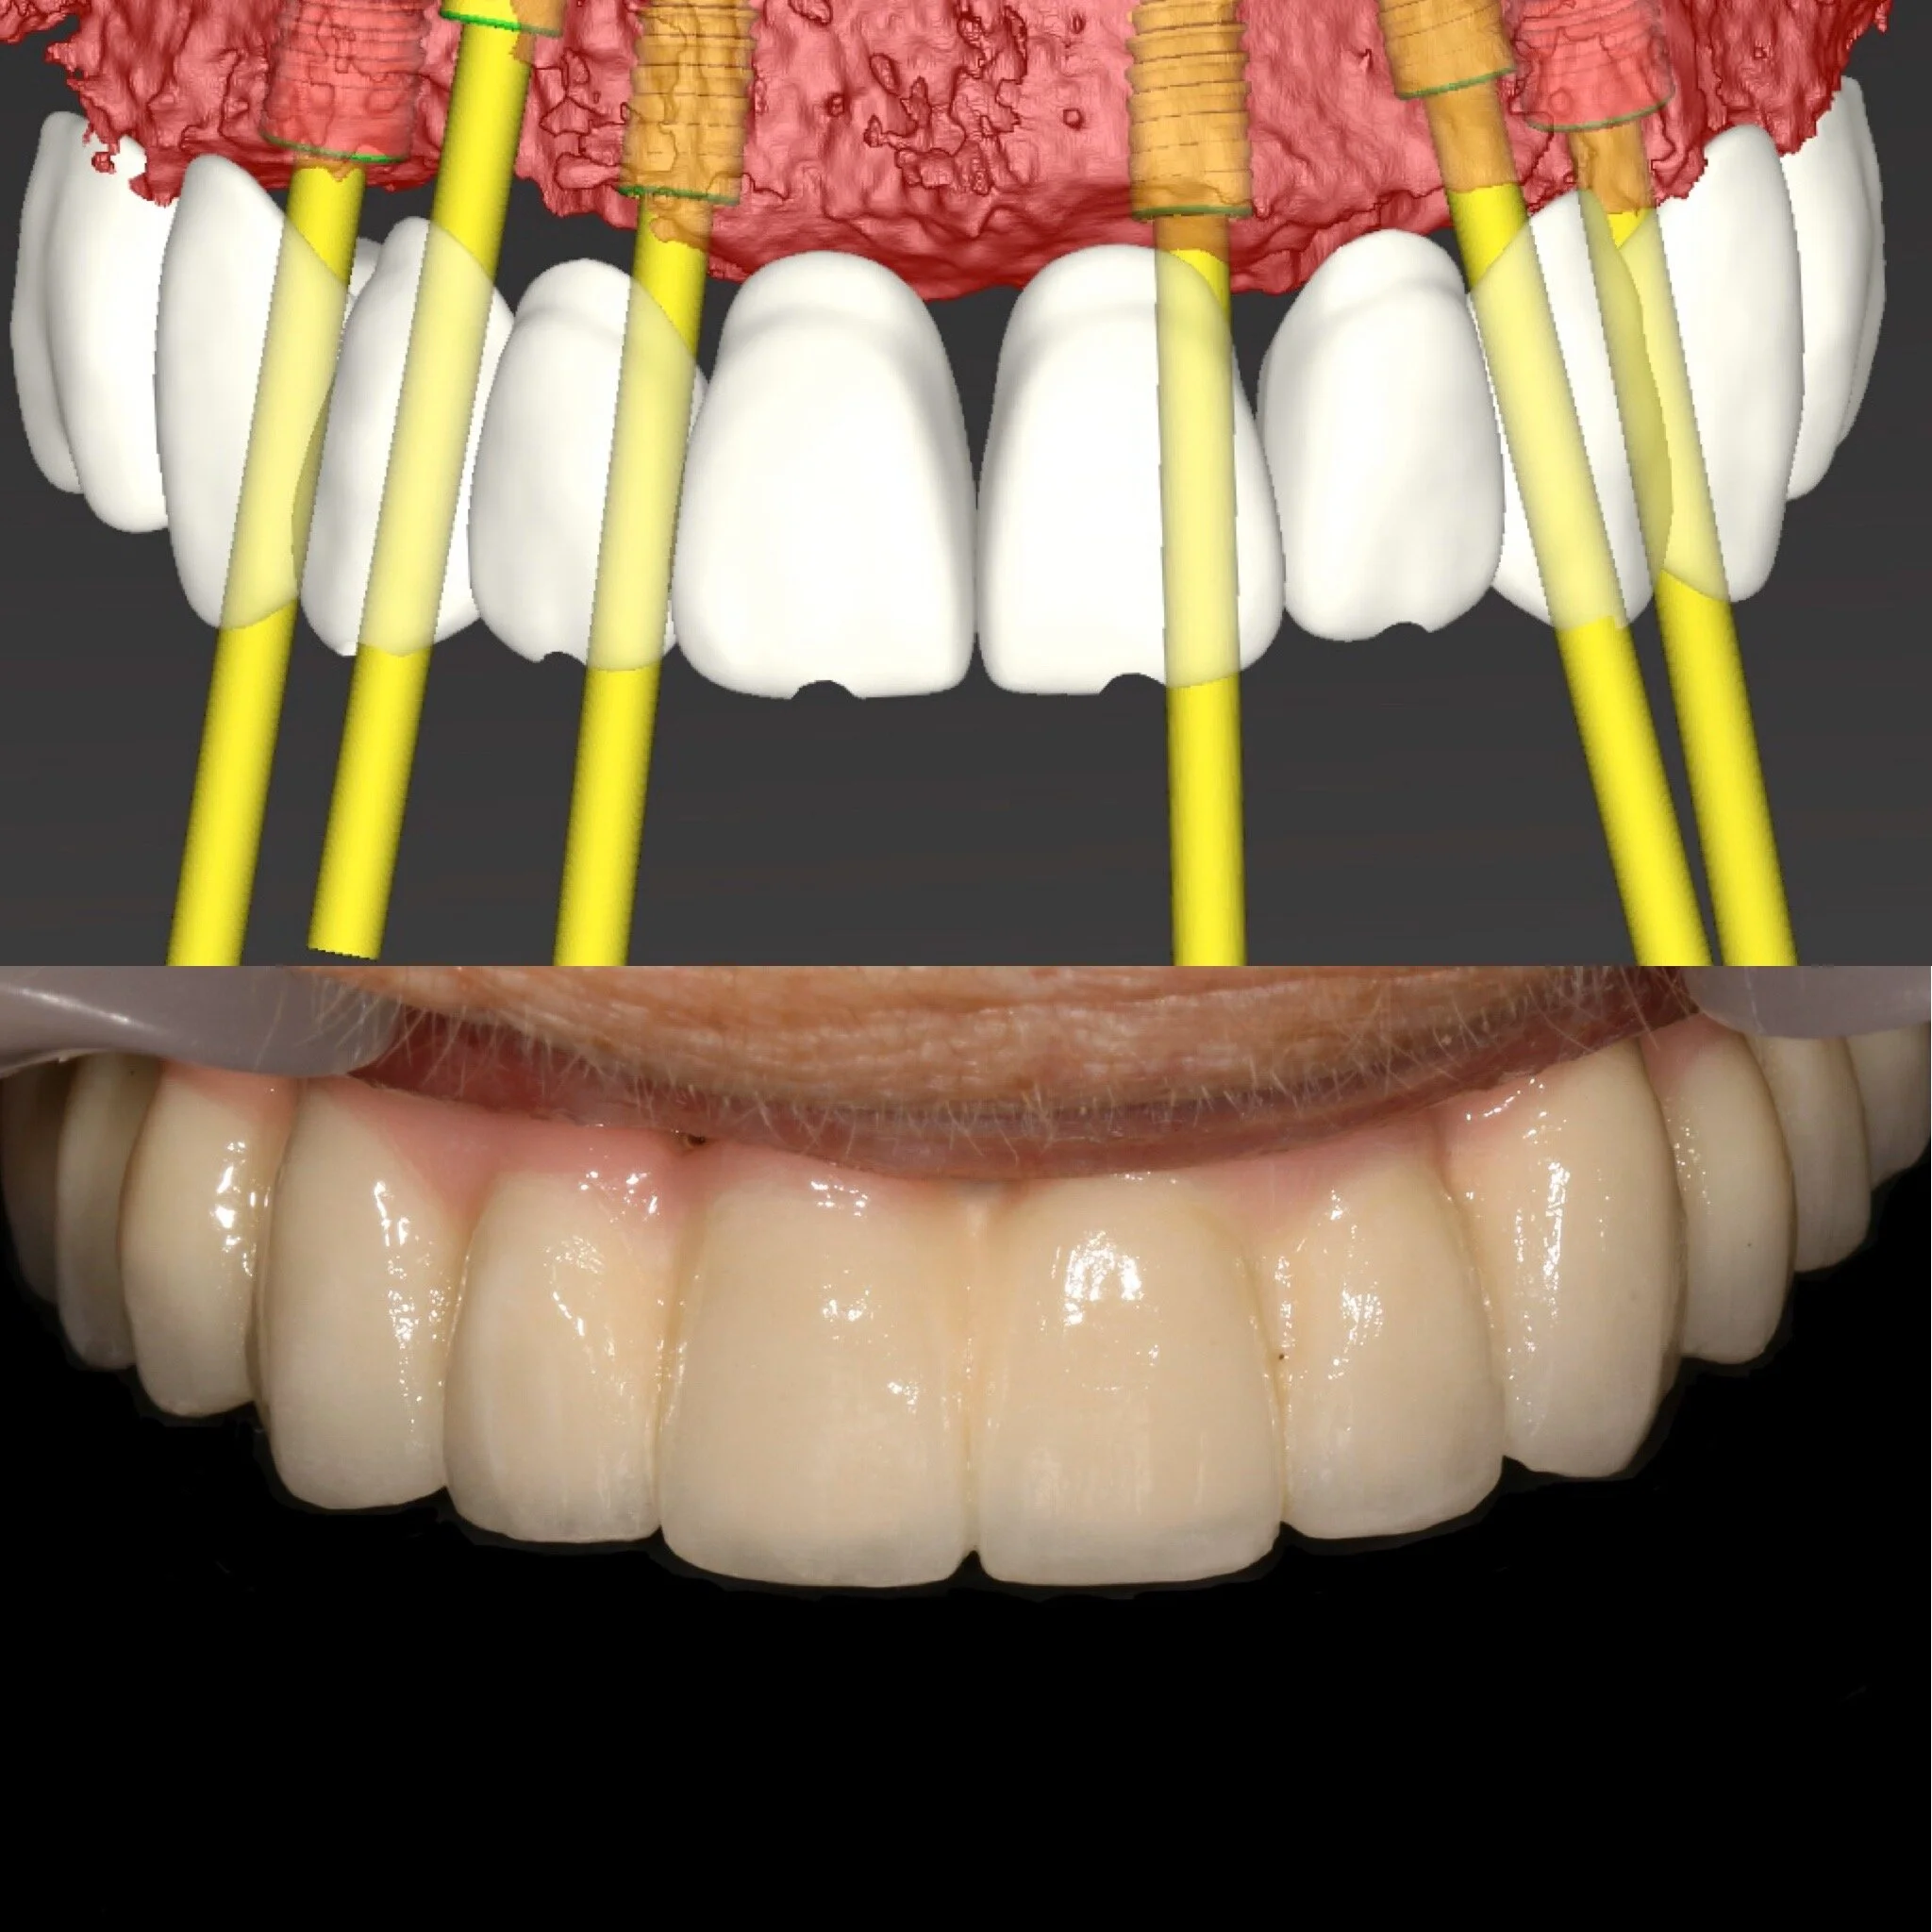

Utredningen kommer sedan att stå som en biologisk grund för Din behandling där faktorer som allmänhälsa, oral hälsa, mediciner, mjukvävnad m.m kommer att studeras. Benvolym utvärdeas med hjälp av avancerad röntgenteknik som avbildar käkarna i 3D. Bilden förs sedan över till ett datorprogram där Dr. Osama planerar behandlingen utifrån Dina förutsättningar. På så sätt kan implantaten placeras med mycket hög precision och kvalitet. Detta för att ge Dig ett resultat som både är biologiskt, funktionellt och anpassat efter just Dina förväntningar/önskemål.